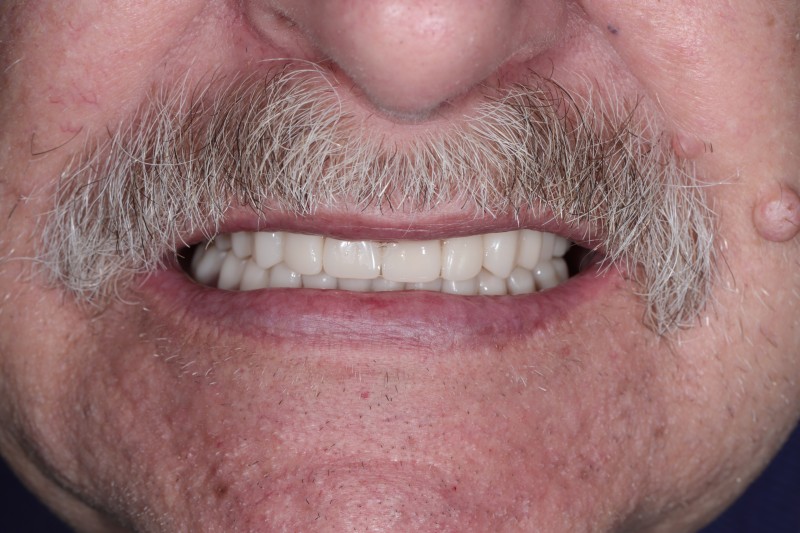

Установка условно-съемного протеза

Удалены все разрушенные и подвижные зубы, установлено по 4 имплантата на верхнюю и нижнюю челюсти, изготовлены съемные протезы с фиксацией на имплантаты.